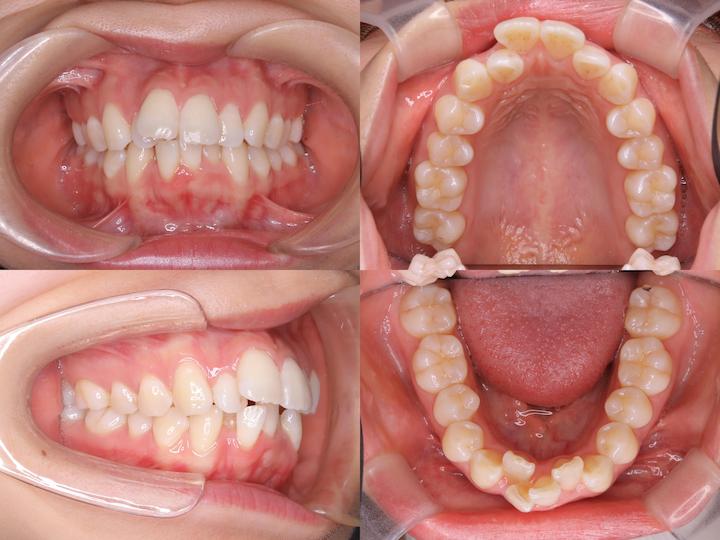

初診時年齢25歳11ヶ月、大阪市内在住の患者様です。歯並びのガタつきと口元の突出感を主訴にご来院されました。

下顎前歯の叢生が重度であったことと口元の突出感があったことから、上下左右第一小臼歯の抜歯が必要と診断しました。